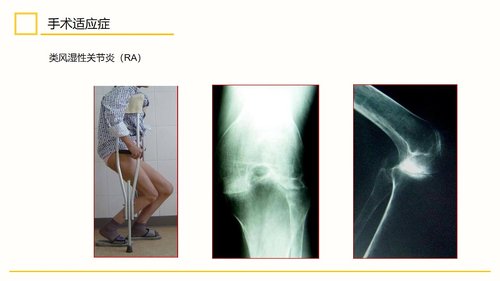

该手术主要适用于膝关节单间室退行性骨关节炎、类风湿性关节炎、强直性脊柱炎、创伤性关节炎、结核或肿瘤术后强直等多种疾病导致的局限性严重疼痛和功能障碍,尤其对于伴有内翻、外翻或屈曲挛缩等畸形的病例具有明确指征。其禁忌症主要包括关节周围或全身活动性感染,以及可能导致全膝置换术后关节不稳的各类疾病。